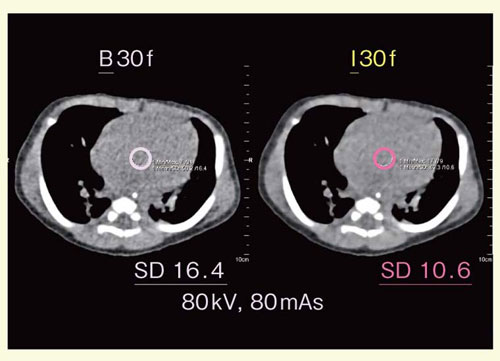

2010”N6ŒŽ‚æ‚èC¬Ž™CT‚É‚¨‚¢‚ÄIRIS‚ª“±“ü‚³‚êC]—ˆ‚Æ“¯ˆêðŒ‚Å‚ ‚ê‚ÎSNR‚ª‰ü‘P‚³‚ꂽB‚Ü‚½C‰æŽ¿ƒŒƒxƒ‹‚𓯓™‚É‚µ‚½ê‡‚É‚ÍC‚æ‚è’áü—ʂł̎B‰e‚ª‰Â”\‚ƂȂÁ‚½BŒ»Ý‚Å‚ÍCŽå‚ÉŠÇ“dˆ³‚ð80kV‚Æ‚µC‘Ìd‚ɉž‚¶‚ÄŠÇ“d—¬‚à20`30“’ö“x‰º‚°‚ÄŽB‰e‚ðs‚Á‚Ä‚¢‚邪C\•ª‚ȉ掿‚ª“¾‚ç‚ê‚Ä‚¢‚éB

œ Ç—á5F‘å“®–¬—£’fÇC‘å“®–¬”x“®–¬‘‹C“®–¬ŠÇŠJ‘¶i}7j

0Î1‚©ŒŽC’jŽ™C‘Ìd3.4kgCS””160bpmBIRIS“±“ü‘O‚ÉŽB‰e‚³‚ꂽǗá‚Å‚ ‚邪CRawƒf[ƒ^‚©‚çFBP–@iB30fj‚ÆIRISiI30fj‚Å‚»‚ꂼ‚êÄ\¬‰æ‘œ‚ð쬂µ”äŠr‚µ‚½BIRIS‚ð—p‚¢‚½‰æ‘œ‚ÅSNR‚ª‰ü‘P‚µ‚Ä‚¢‚邱‚Æ‚ª‚í‚©‚éB

}7@Ç—á5F‘å“®–¬—£’fÇC‘å“®–¬”x“®–¬‘‹C“®–¬ŠÇŠJ‘¶i0Î1‚©ŒŽC’jŽ™j